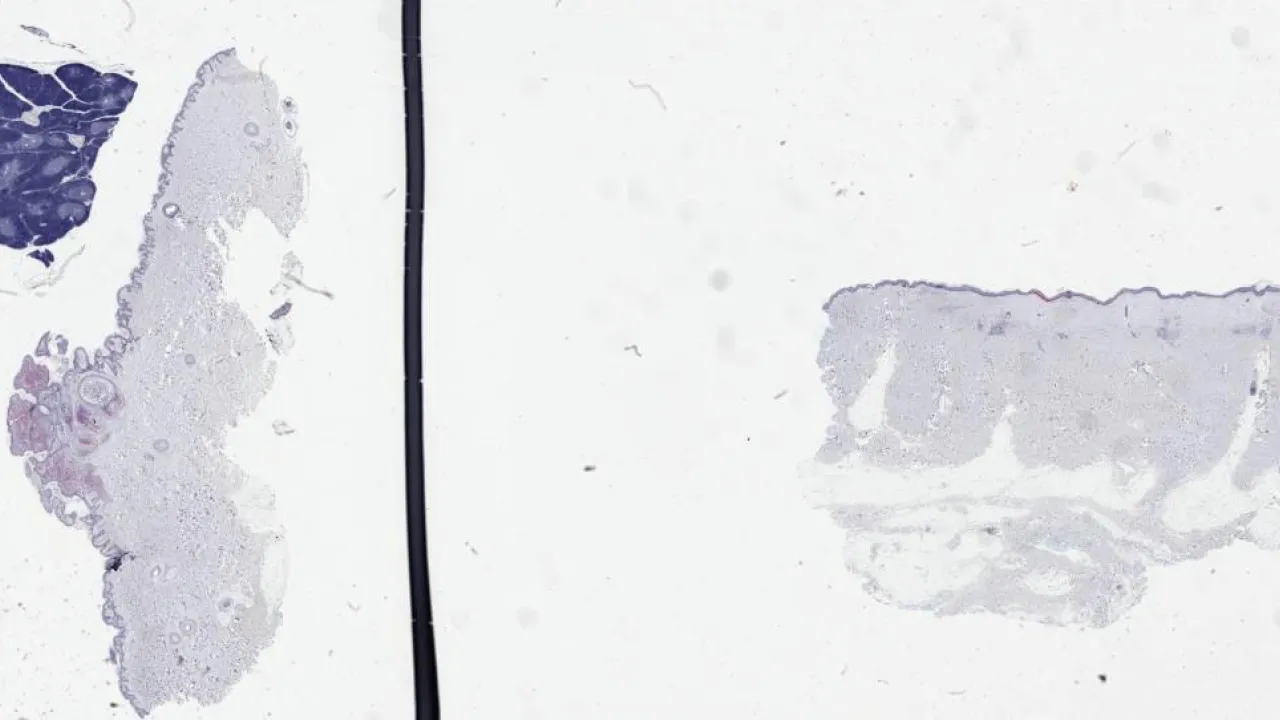

Skin, Recurrent nevus phenomenon, H&E stain

Skin, Recurrent nevus phenomenon, Melan-A stain

Cervix, Low-grade squamous intraepithelial lesion